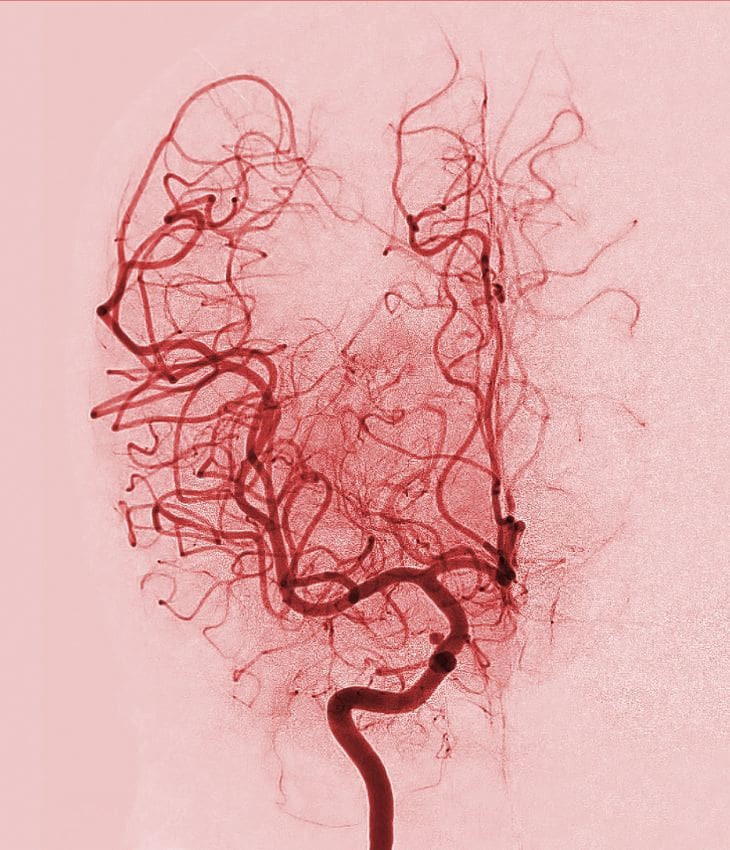

Coronary angiography is a gold-standard test used to visualise the heart’s arteries and detect blockages or narrowing. As a leading consultant cardiologist and internationally recognised expert in coronary physiology, I use advanced techniques to deliver accurate, minimally invasive diagnosis.

During the procedure, a thin catheter is inserted into the wrist or groin and guided to the heart. Contrast dye is injected, and X-ray images reveal the condition of the coronary arteries. This procedure helps determine the best treatment – such as stenting or bypass surgery. Performed under local anaesthetic, most patients return home the same day.